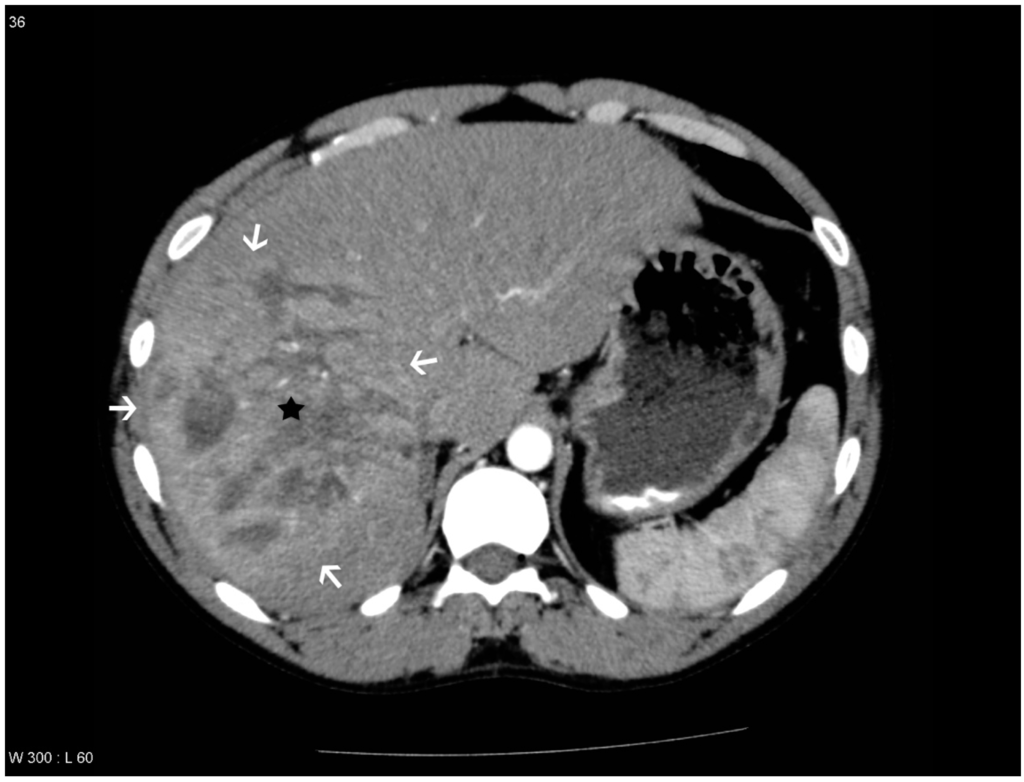

Figure 1. Patient with a pseudoaneurysm within the liver lesion in segment 2, which was confirmed by digital subtraction angiography (DSA) and treated with embolization. Areas with transient hepatic attenuation difference (THAD) surround the lesion. The liver lesion is marked with a black star, the areas with THAD are marked with white arrows and the pseudoaneurysm is marked with a black arrowhead.

THAD was defined as an increased arterial enhancement in relation to the liver lesion without resemblance of PS/AF. THAD after liver trauma has previously been described as a localized arterial enhancement with a polymorphous appearance [16,18]. The senior radiologist did not comment on THAD in the initial reading, primarily because THAD is regarded as a benign phenomenon. Therefore, presence of THAD was defined by a consensus between at least two out of three observers (residents in radiology) (Figure 1, Figure 2, Figure 3 and Figure 4).

PS/AF can be recognized and distinguished from THAD by the location, the appearance, and the HU level. PS/AFs seen in 14% of the patients were all oval or round except one, which was linear, and all had focal enhancement with mean HU levels of 170. All PS/AFs were found within the liver lesions (Figure 1 and Figure 4). PS and AF were indistinguishable as stated previously by others [9]. Areas with THAD seen in 54% of the patients had hazy borders, were all found in the periphery of the lesion and with mean HU levels of 100 (Figure 1, Figure 2, Figure 3 and Figure 4).